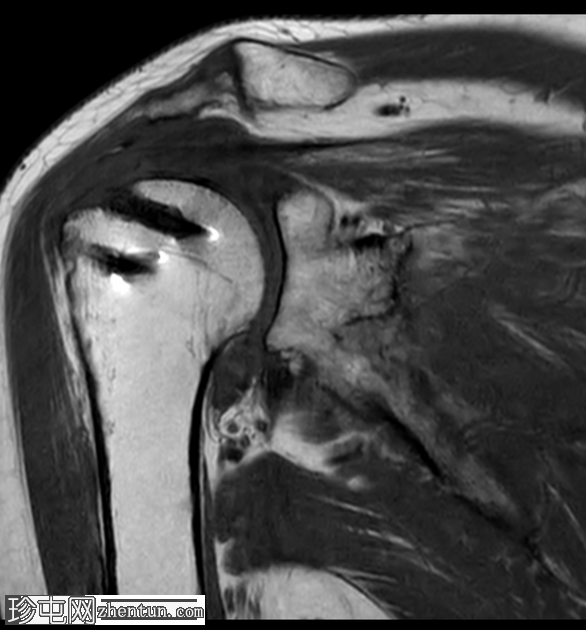

轴位

PD加权像

冈上肌腱后侧纤维显示全层撕裂,其特征为液体信号贯穿肌腱全层。该撕裂处可见少量低信号灶,可能代表脱落的锚钉碎片。

冈上肌腱锚钉附着点处的前侧纤维显示高T2信号,符合高等级部分撕裂。